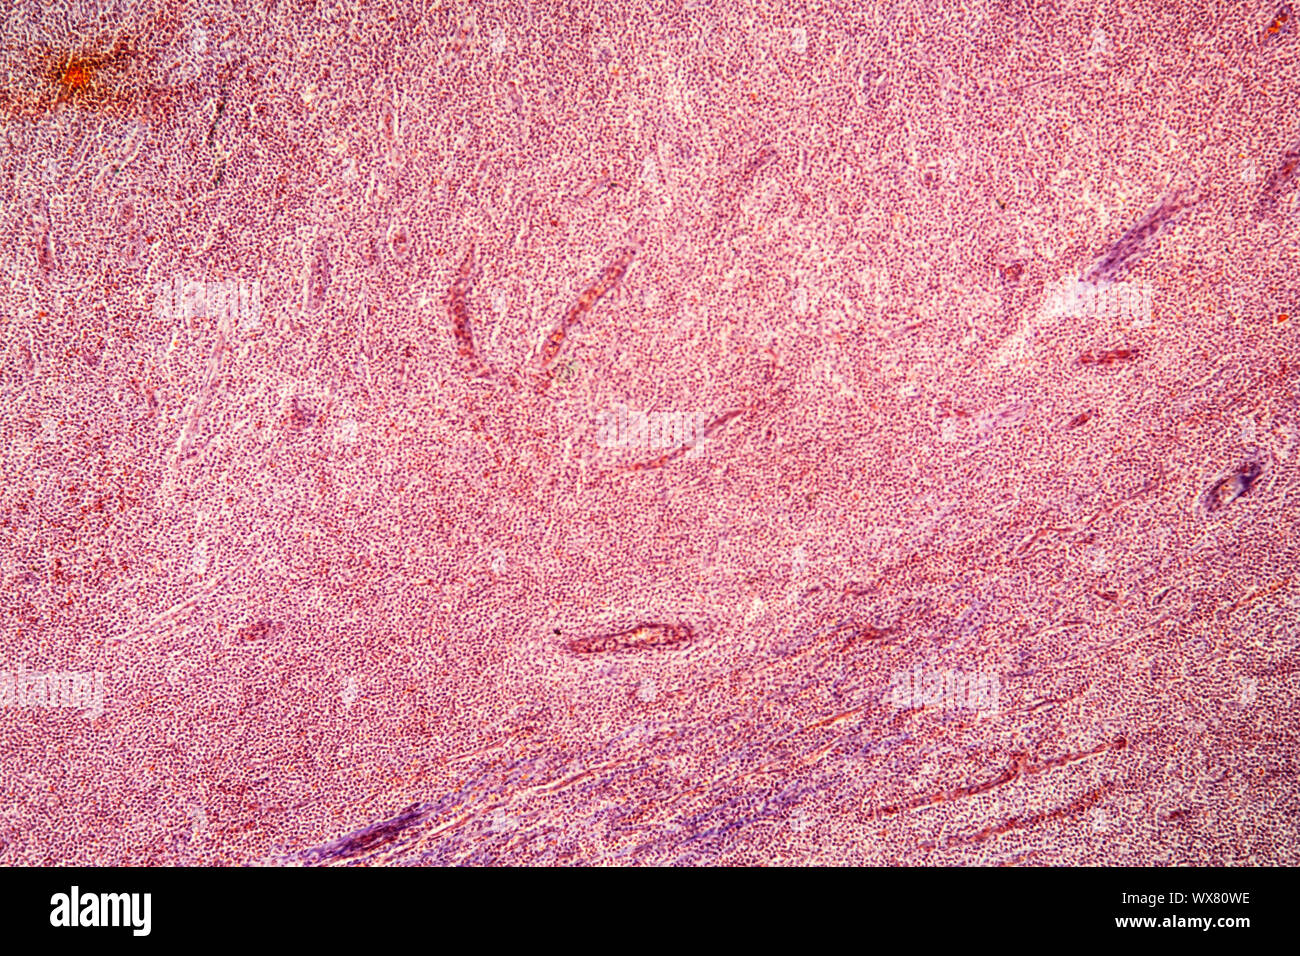

Mandelentzündung krankes Gewebe 100x Stockfotohttps://www.alamy.de/image-license-details/?v=1https://www.alamy.de/mandelentzundung-krankes-gewebe-100x-image227729286.html

Mandelentzündung krankes Gewebe 100x Stockfotohttps://www.alamy.de/image-license-details/?v=1https://www.alamy.de/mandelentzundung-krankes-gewebe-100x-image227729286.htmlRFR6DY0P–Mandelentzündung krankes Gewebe 100x